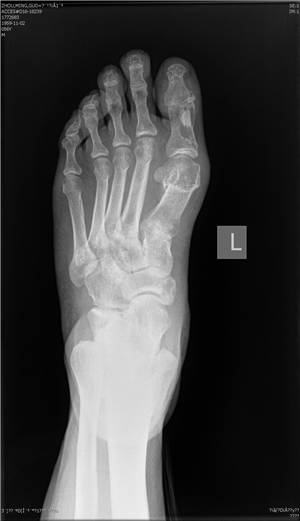

传统方法(左)与微创矫形方法(右)对比

微创矫形方法术前(左)术后(右)X光对比